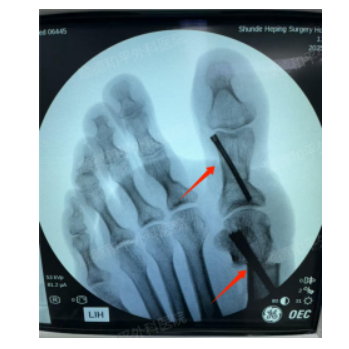

并细心地介绍了我院目前对拇外翻治疗,已更新到了最新的术式——第四代微创拇外翻手术(MICA),手术优势:包括旋前纠正、固定强度和减少复发的步骤,同时结合主动的三维复位操作,以矫正所有畸形平面,用两个螺钉进行刚性稳定的双皮质固定,以允许早期的负重和康复。

手术耗时也很短,仅1个多小时,只在左足患处各留下三个0.3cm的小切口,术中出血量少,术后恢复速度也更快。严格按照术前设计精准矫形,整个手术过程严谨、精细且高效。细致的诊查结合摄片综合判定,韦女士的情况可以通过该术式进行治疗。

5月7日,安排好个人时间的韦女士,再次返回到我院接受第四代微创拇外翻手术(MICA)治疗。在程忠勇主任及其团队的精心操作下,手术进展十分顺利。手术第二天,韦女士就能穿前足减压鞋逐步下床活动,患者恢复状况良好,术后三天成功出院。